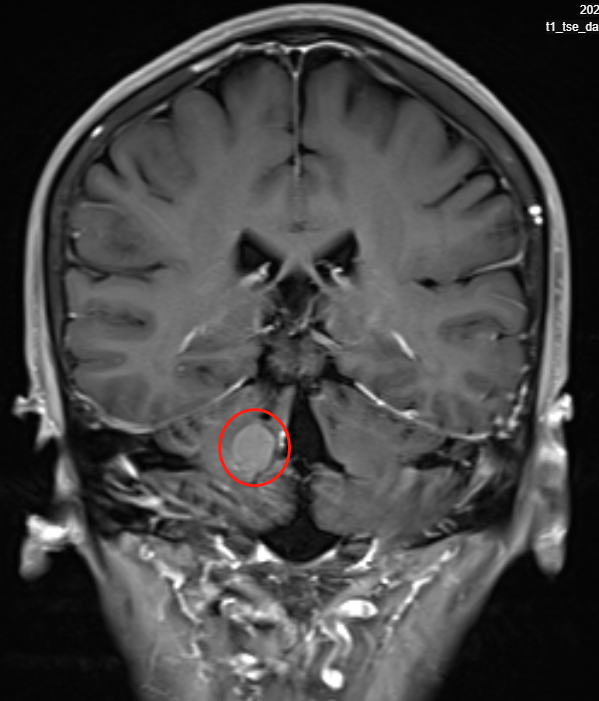

病情回顾:40多岁的赵女士因耳呜到医院检查,本以为是耳朵出了小毛病,但较后核磁检查发现右侧小脑海绵状血管瘤伴出血,大小约10mm,几天后耳呜症状消失,侍观察故无不同处理。然而距离发现仅过去5个月,赵女士就出现了头晕、头痛、呕吐,完事CT检查结果提示病灶未出血。2022年6月20日,复查CTA发现病灶再次出血。进行核磁共振检查提示:右侧小脑顶部海棉状血管瘤、右侧桥臂出血灶,国内医生建议手术治疗,但表示术后患者的症状无法完全消失,并且有症状加重的可能。听到这个答案,原本就饱受疾病折磨的赵女士情绪更加低落,如果手术后症状不但不会好转还会加重的话,那冒险手术的意义在哪里呢?